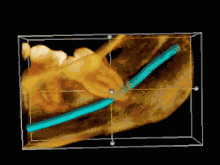

Risk factors of inferior alveolar nerve damage

Temporary and permanent inferior alveolar nerve (IAN) damage is a known complication of the surgical removal of impacted lower third molars, happening in 1 in 85 patients and 1 in 300 extractions, respectively. Studies have shown that certain risk factors may increase the likelihood of IAN damage. Proximity of the impacted third molar root to the mandibular canal, which can be seen in radiographs, has been shown to be a high-risk factor for IAN damage. Alongside this, the depth of impaction of the tooth, surgical technique and surgeons experience are all contributing risk factors for IAN damage during this procedure. Careful case-by-case consideration is crucial to avoid this risk.[43]